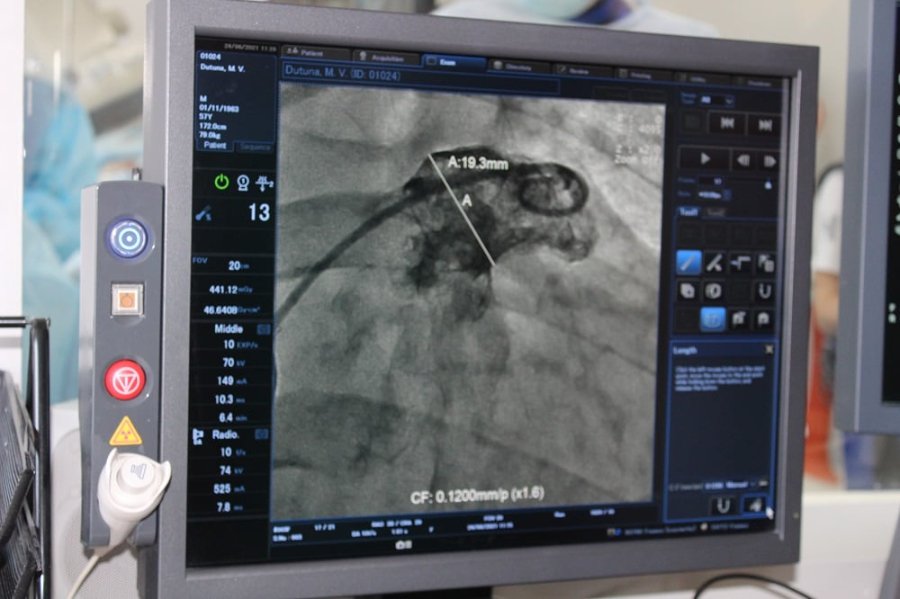

Обидві операції пройшли успішно. Їх проводили за допомогою ангіографа (із застосуванням рентгенологічного обладнання) через прокол у судині на нозі і не потребували хірургічних розрізів.

Пацієнтам імплантовано спеціальний пристрій - оклюдер останнього покоління UltraSept LAA виробництва CARDIA (USA).